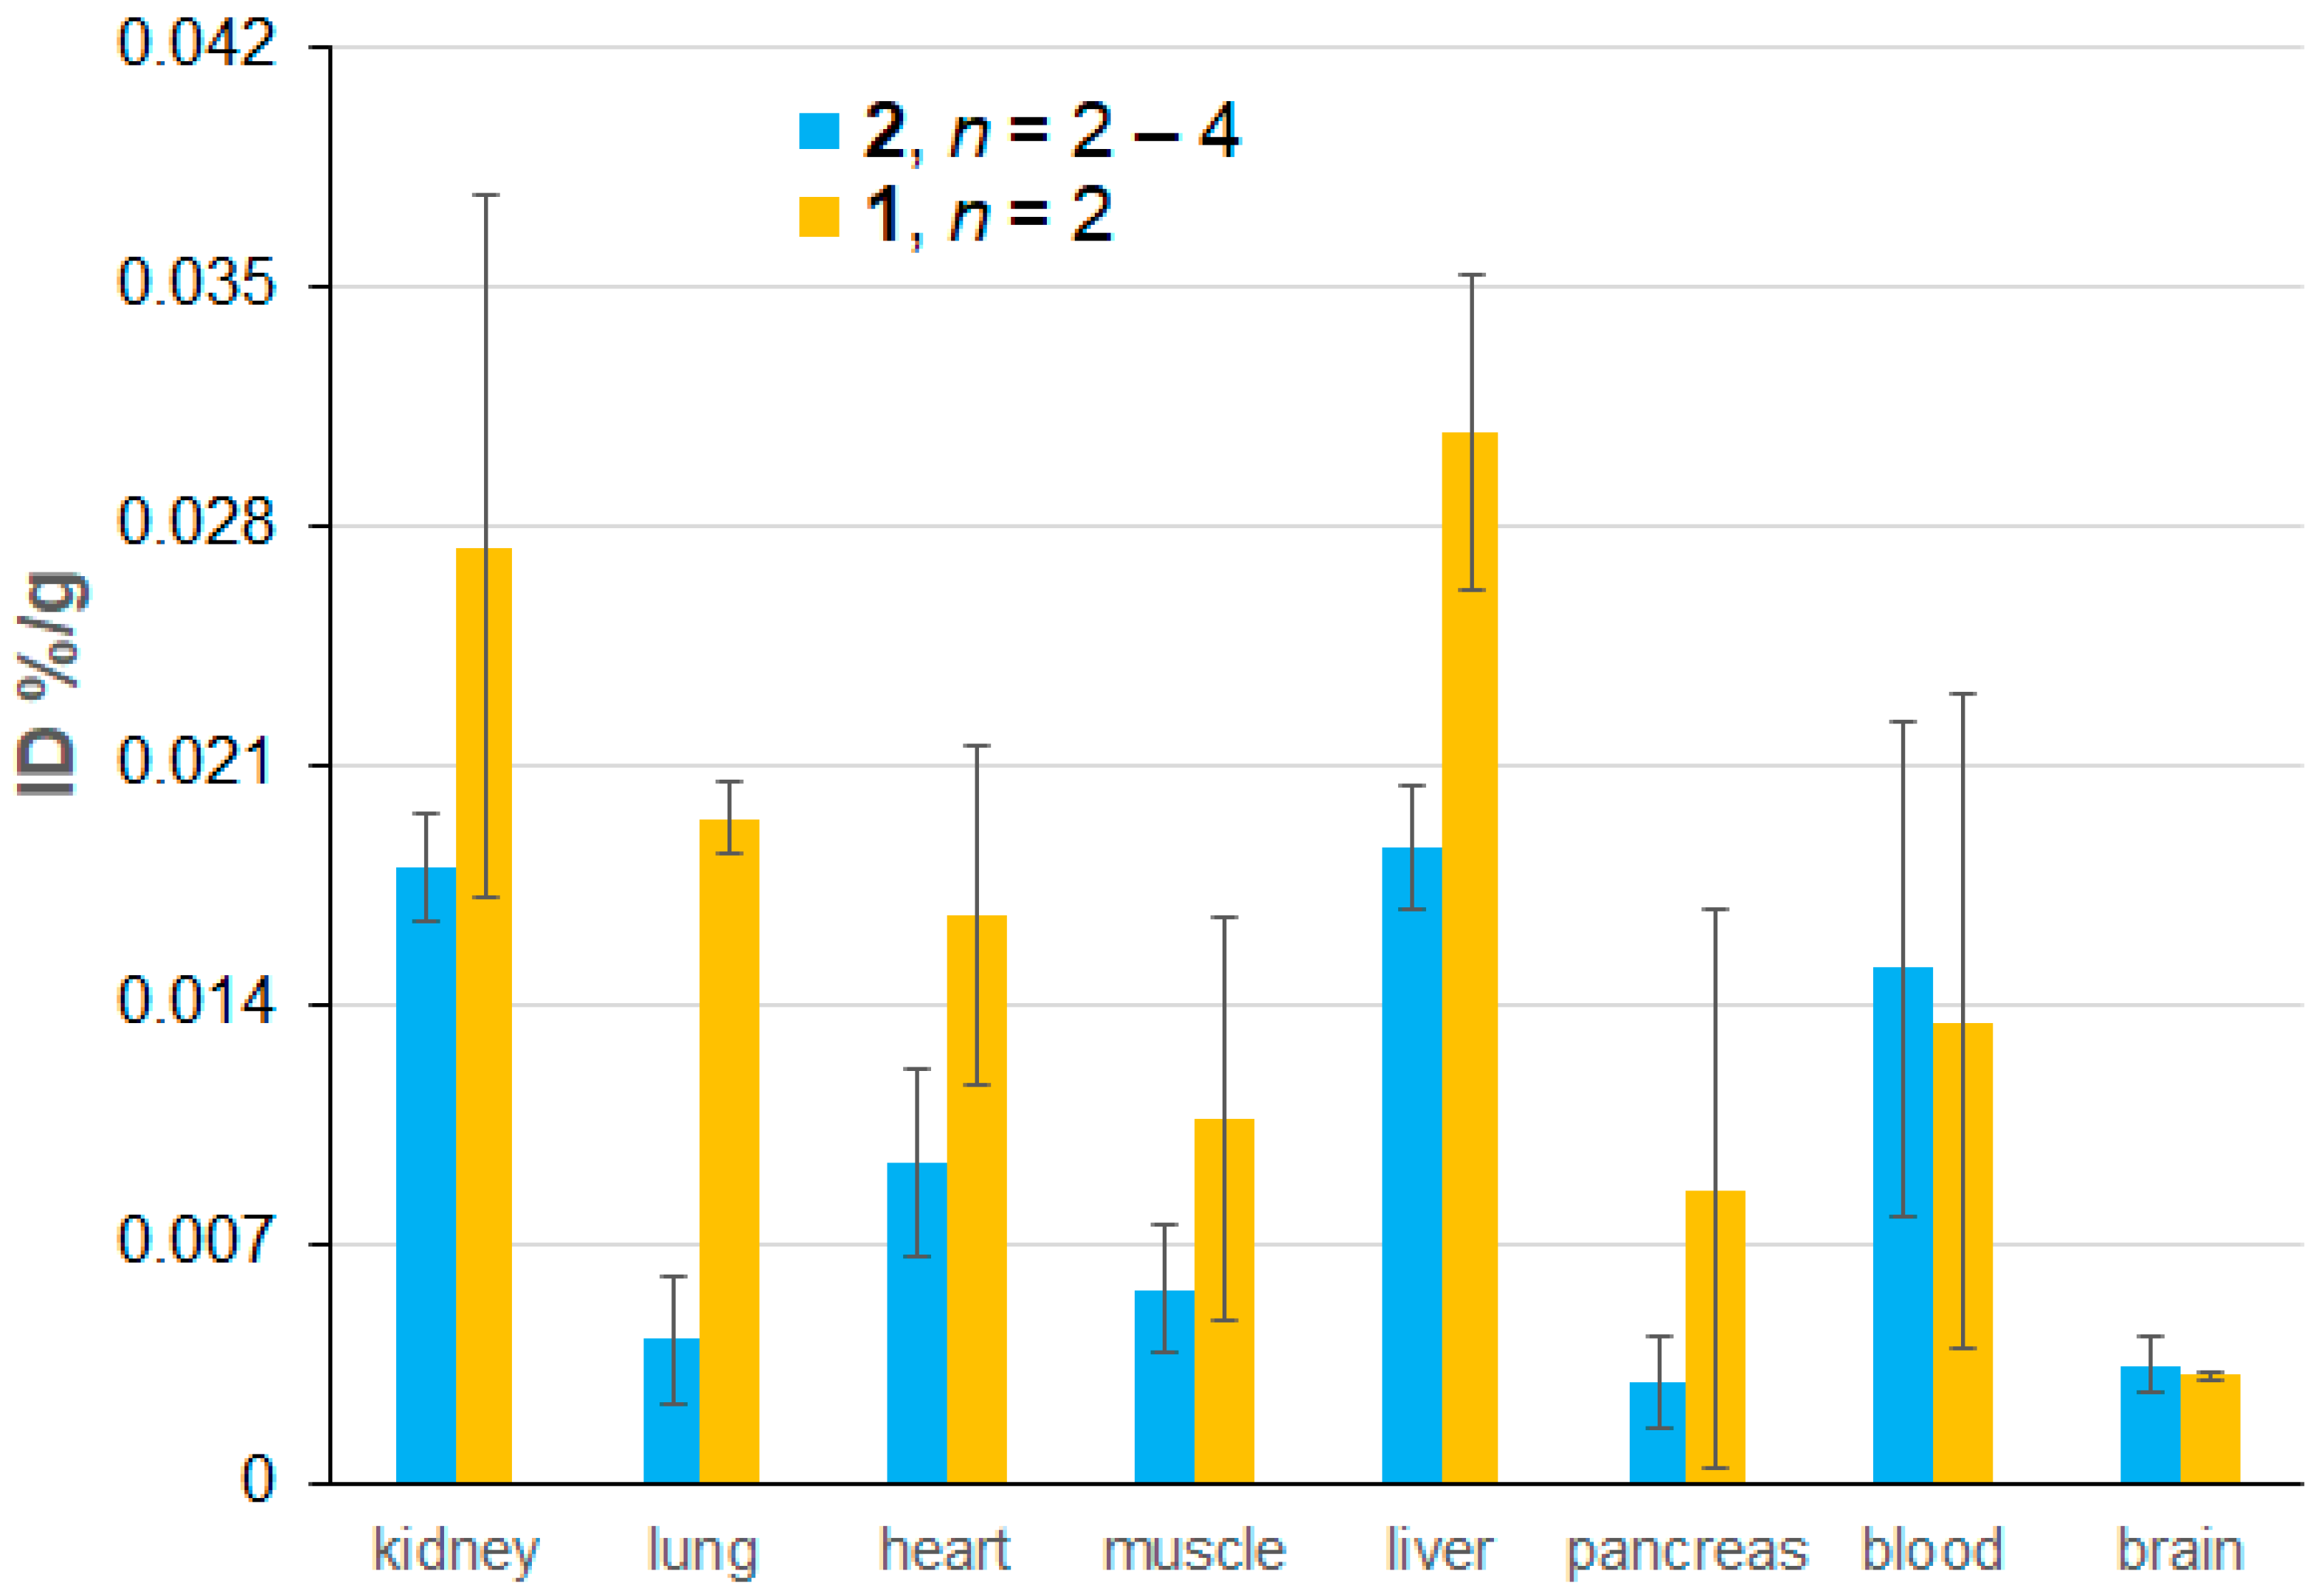

2.4. Ex Vivo EPR Spectroscopy of 1 and 2

| Tissue | mORCA 1 | mORCA 2 | ORCAFluor | ||

|---|---|---|---|---|---|

| %ID (n) | % 1 | %ID (n) | % 1 | %ID | |

| Blood | 0.014 ± 0.010 (2) | 0.24 | 0.015 ± 0.007 (4) | 0.27 | 5.6 ± 0.7 |

| Kidney | 0.027 ± 0.010 (2) | 5.7 | 0.018 ± 0.002 (4) | 3.8 | 0.48 ± 0.06 |

| Liver | 0.031 ± 0.005 (2) | 10.8 | 0.019 ± 0.002 (4) | 6.6 | 0.28 ± 0.08 |

| Lung | 0.020 ± 0.001 (2) | 1.7 | 0.004 ± 0.002 (4) | 0.36 | 1.2 ± 0.2 |

| Heart | 0.017 ± 0.005 (2) | 2.5 | 0.009 ± 0.003 (4) | 1.4 | 0.67 ± 0.10 |

| Pancreas | 0.009 ± 0.008 (2) | na | 0.003 ± 0.001 (4) | na | na |

| Muscle | 0.011 ± 0.006 (2) | na | 0.006 ± 0.002 (3) | na | na |

| Spleen | 0.019 ± 0.004 (2) | 2.6 | 0.023 ± 0.007 (2) | 3.2 | 0.72 ± 0.14 |

| Brain | 0.0032 ± 0.0001 (2) | na | 0.0035 ± 0.0008 (2) | na | <<0.001 |